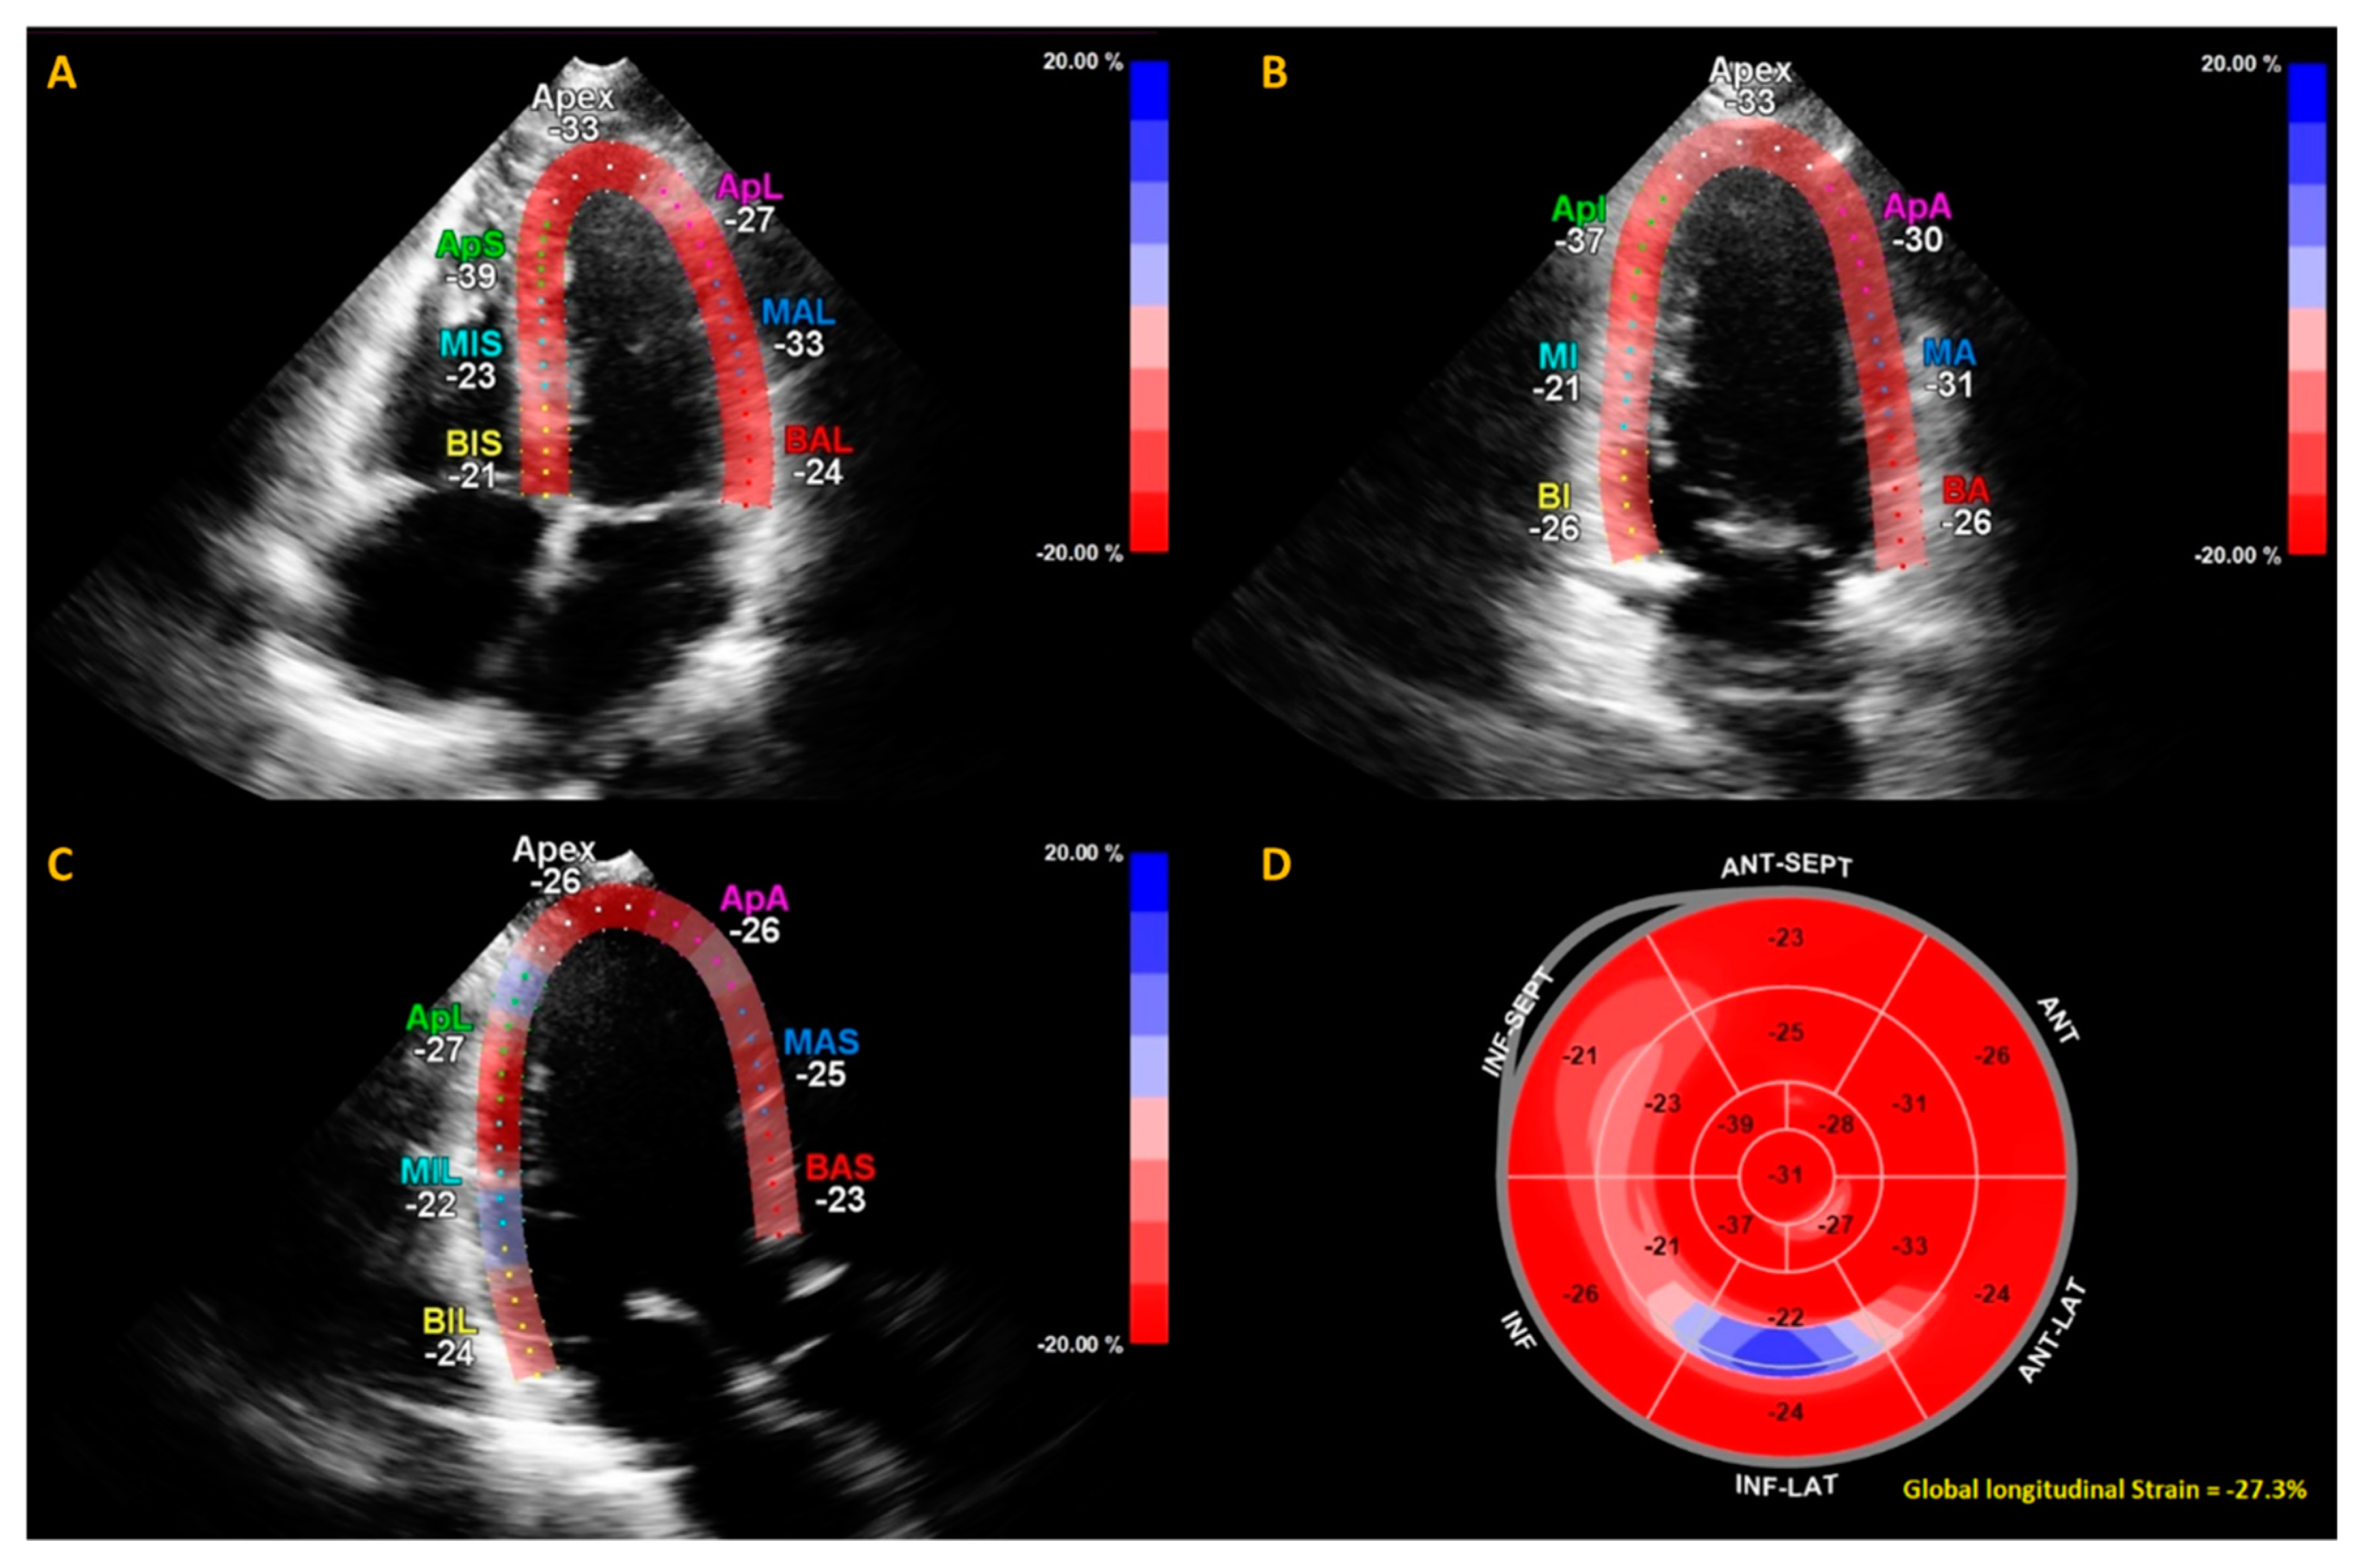

Example of calculation of global longitudinal strain (GLS) by speckle tracking for the apical four-, three- and two-chamber views (A–C). The strain during one cardiac cycle is shown for each of the color-coded (red and blue) left ventricular segments. The longitudinal strain bull’s eye plot (D) determined from 2D speckle tracking imaging offers a visual overview of the regional and global left ventricular myocardial function in a diagram. In this example of one of the subjects in this study, the GLS is −27.3%, which is in the normal range.

Echocardiography—transthoracic echocardiography (TTE)—was performed by certified echo technicians at the European Society of Cardiology (ESC)-certified department of echocardiography of the Amsterdam University medical center, location VUmc, using a Philips ultrasound system (Epiq 7 and IE 33, Philips, Amsterdam, NL). All echocardiographic recordings were stored digitally and were afterwards analyzed by an experienced cardiologist specialized in echocardiography (T.C.K.). TTE was performed according to the following protocol based on the guidelines provided by European Association of Echocardiography [26]. Assessment of the cardiac function consisted of apical four-, three- and two-chamber views, and 2D color and spectral flow Doppler recordings. Left ventricular mass (LVM) was computed based on the Devereux and Reichek formula [27]. Pulse wave tissue Doppler imaging was assessed in the apical views to obtain mitral annular velocities. The sample volume was located at, or within 1 cm of the septal (e’ sept) and lateral (e’ lat) mitral valve insertion sites. Doppler spectral velocity recordings of the mitral inflow were assessed with the sample volume aimed at the tips of mitral valves. From the trans mitral Doppler velocity recordings, the E wave deceleration time (DT), peak E and A velocities and the E/A ratio were acquired. Left atrial volume was obtained using the modified biplane Simpson’s rule. LVEF and diastolic and systolic volumes were computed by Simpson’s from the apical four- and two-chamber view. The left ventricular global longitudinal strain (GLS) was measured using QLab (version 10.3, Philips, Amsterdam, NL) (Figure 1). As the quality of echocardiography is subject to external factors such as excessive fat tissue, not all cardiac parameters were assessed per patient. The total number of cardiac parameter assessments are therefore described per variable in Table 1.